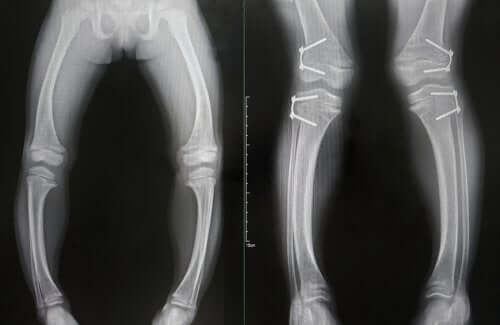

- Deformations in the bones, which soften. This condition is likely to cause bowed legs in the sufferers. It can also cause wear on the ends of some bones.

The diagnosis of this condition is based on the combination of altered analytical and radiographic findings and the presence of the typical clinical symptoms we explained above.